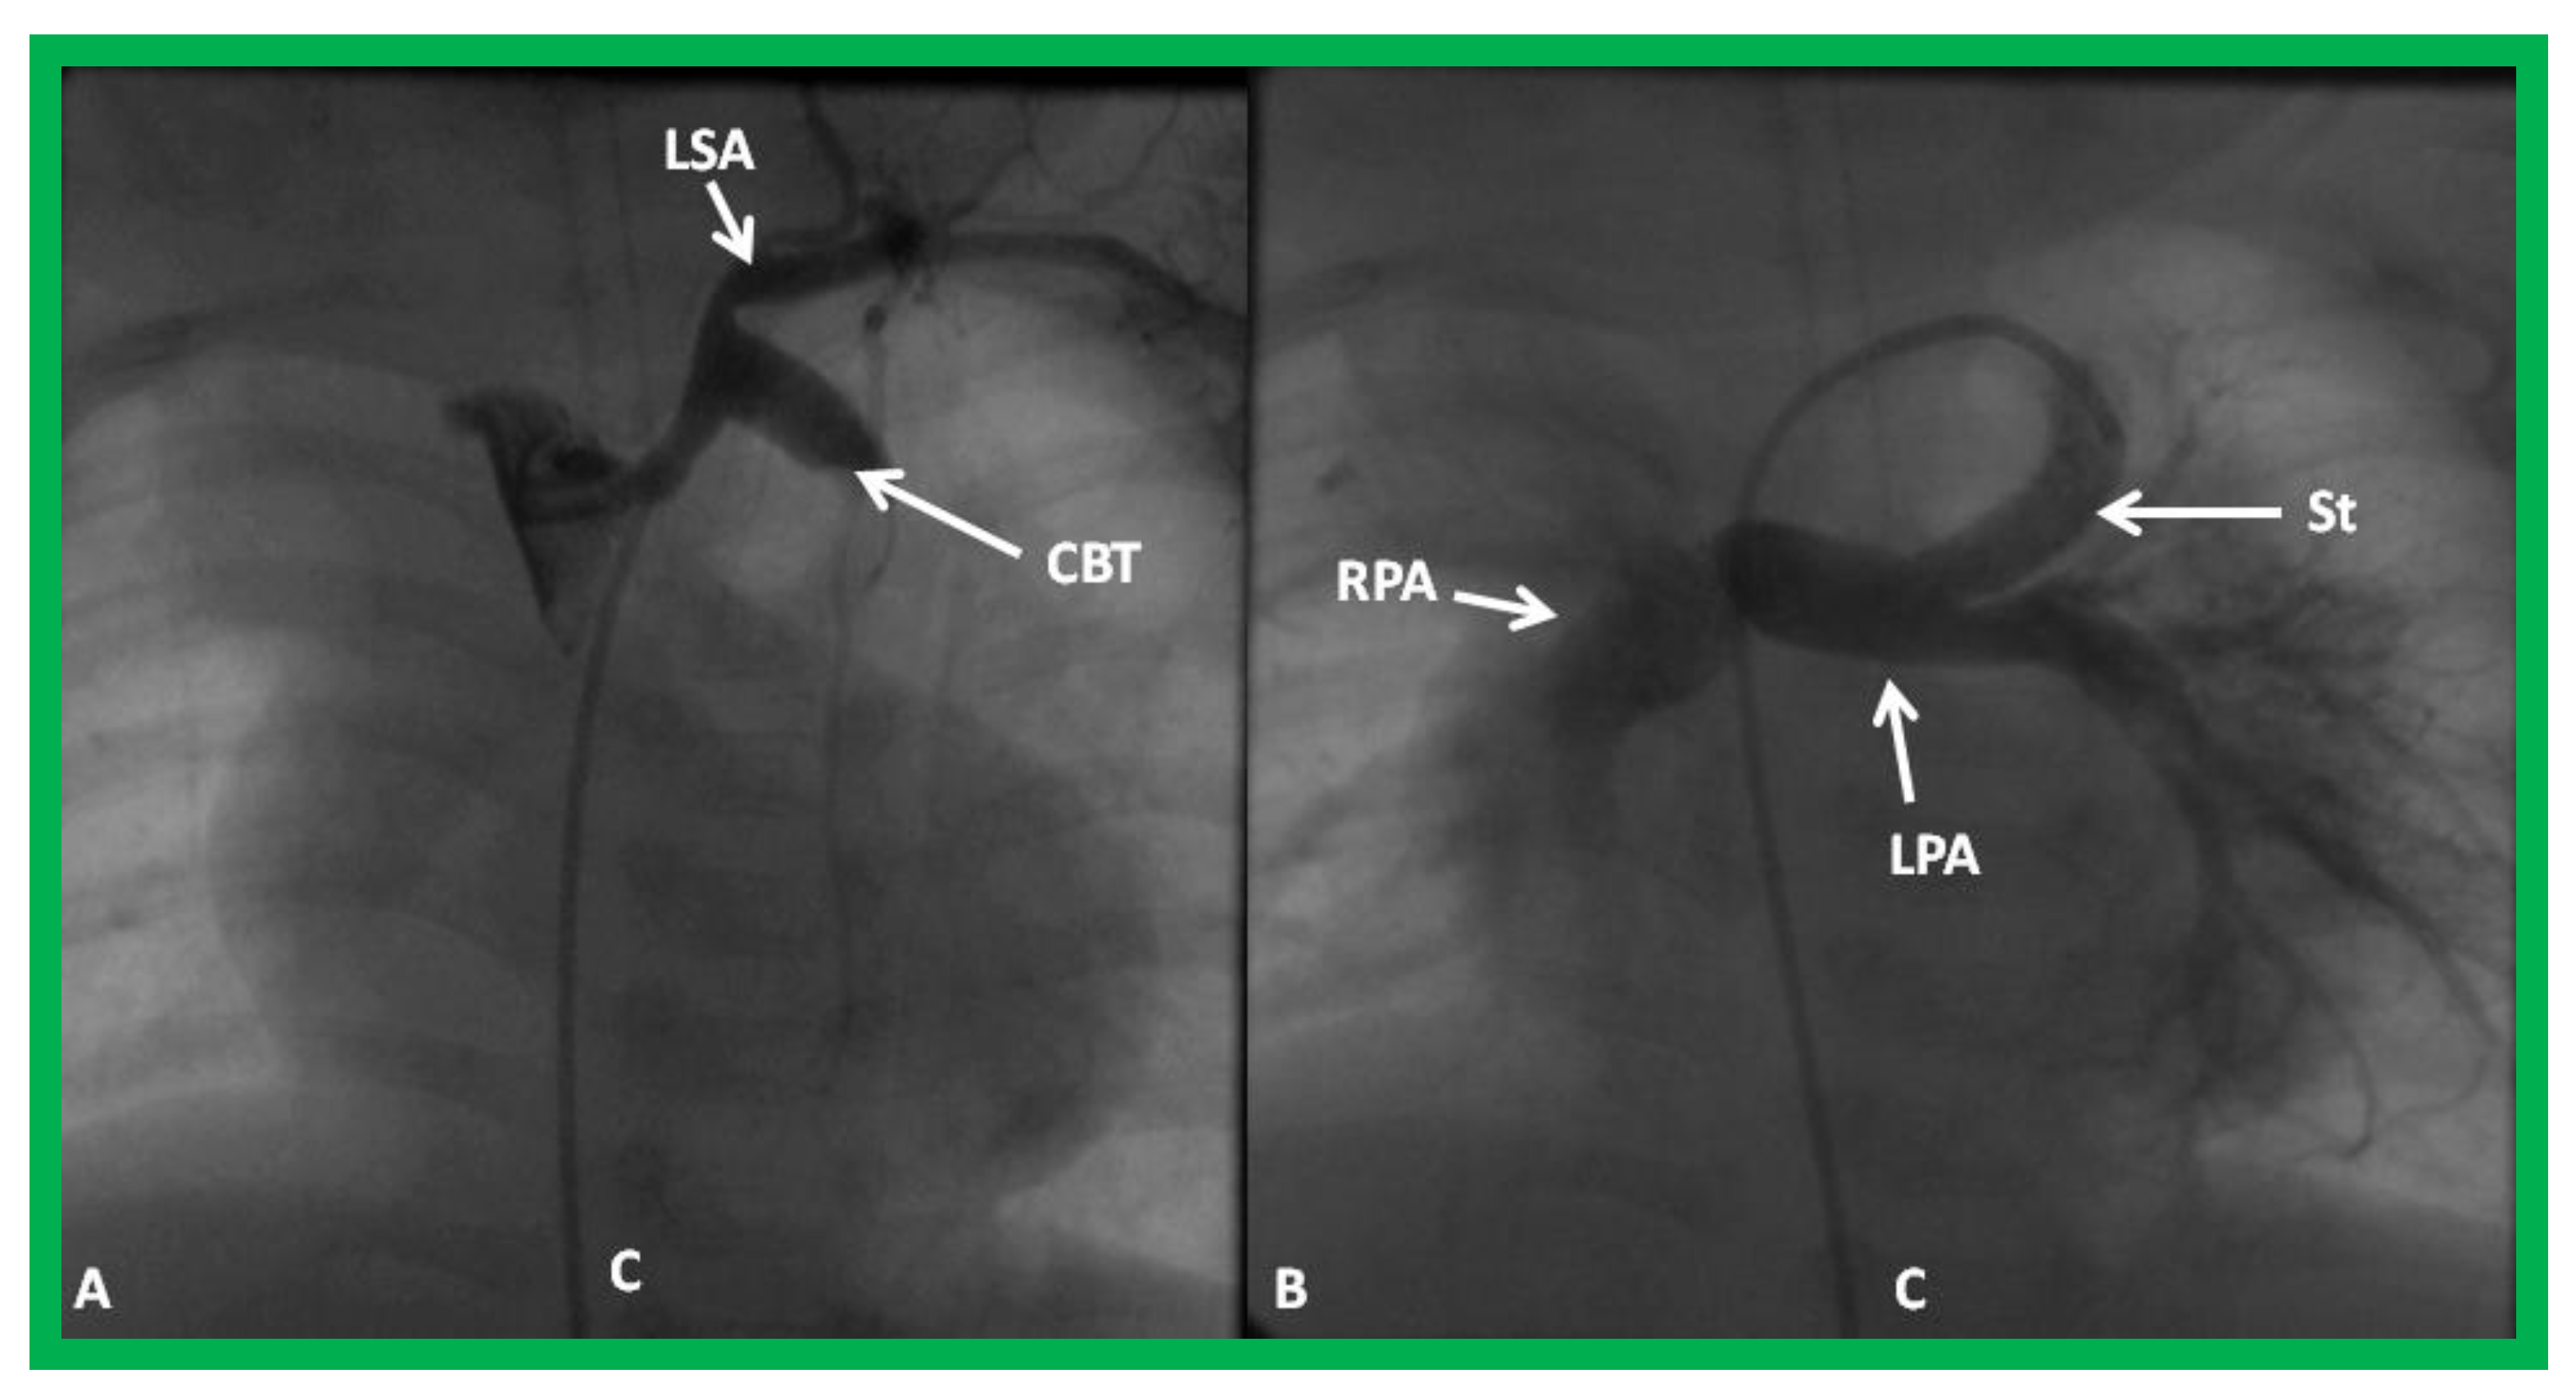

- Akintuerk, H.; Michel-Behnke, I.; Valeske, K.; Mueller, M.; Thul, J.; Bauer, J.; Hagel, K.; Kreuder, J.; Vogt, P.; Schranz, D. Stenting of the arterial duct and banding of the pulmonary arteries: Basis for combined Norwood stage I and II repair in hypoplastic left heart. Circulation 2002, 105, 1099–1103. [Google Scholar] [CrossRef] [PubMed]

- Galantowicz, M.; Cheatham, J.P. Lessons learned from the development of a new hybrid strategy for the management of hypoplastic left heart syndrome. Pediatr. Cardiol. 2005, 26, 190–199. [Google Scholar] [CrossRef] [PubMed]

- Photiadis, J.; Sinzobahamvya, N.; Hraška, V.; Asfour, B. Does bilateral pulmonary banding in comparison to Norwood procedure improve outcome in neonates with hypoplastic left heart syndrome beyond second-stage palliation? A review of the current literature. J. Thorac. Cardiovasc. Surg. 2012, 60, 181–188. [Google Scholar] [CrossRef] [PubMed]

- Hsia, T.Y.; Cosentino, D.; Corsini, C.; Pennati, G.; Dubini, G.; Migliavacca, F. Modeling of Congenital Hearts Alliance (MOCHA) Investigators. Use of mathematical modeling to compare and predict hemodynamic effects between hybrid and surgical Norwood palliations for hypoplastic left heart syndrome. Circulation 2011, 124 (Suppl. 11), S204–S210. [Google Scholar] [CrossRef] [PubMed]